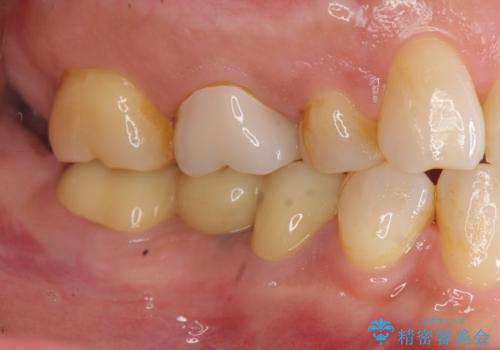

くいしばりで割れたブリッジの支台歯 インプラント再補綴

- 「数年前に入れたブリッジがぐらぐらする、診て欲しい。」と来院されました。

ブリッジを支える歯が割れてしまい、抜歯が必要であることと、骨の大きな吸収が見られました。